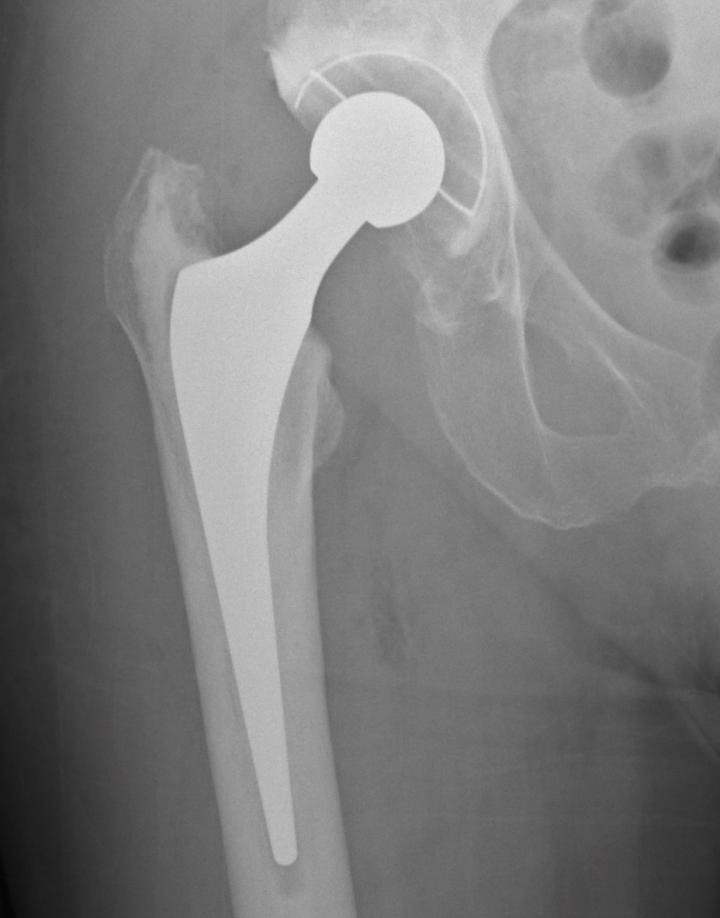

Les fractures de maluc eleven el risc de mortalitat en persones majors

L'evidència científica recolza aquesta preocupació.